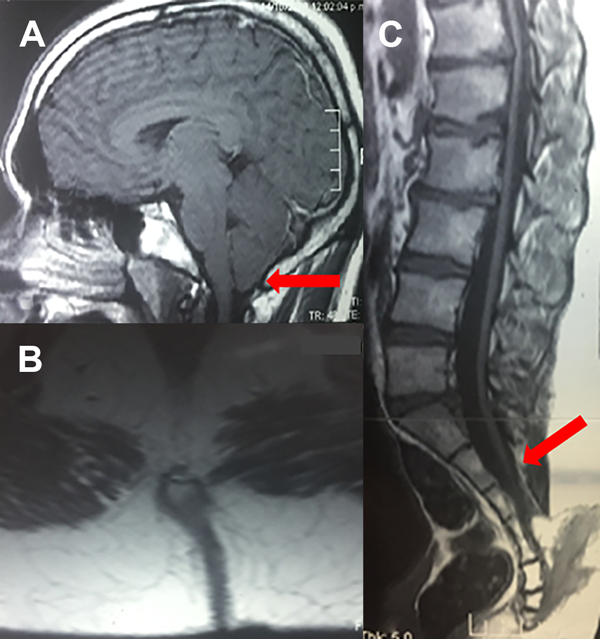

La RM de cerebro mostró descenso de las amígdalas cerebelosas por debajo del foramen magno de 3 mm. Y la RM de columna evidenció en el plano sagital, el cono medular deformado con médula anclada que se proyectaba hacia el segmento lumbosacro. El plano axial mostró disrafia posterior de los segmentos sacros inferiores con lesión que comprometía parcialmente el canal raquídeo sacro, de señal heterogénea compatible con componente graso, y extensión en forma de brecha que se proyectaba hacia tejidos subcutáneos de la región (Figura 2).

Figura 2. a) RM de cerebro que muestra descenso de amígdalas cerebelosas. b,c) RM de columna lumbosacra secuencia T1, cortes axial y sagital que evidencian un trayecto fistuloso descendente a nivel sacro que llega hasta el coxis. Además se observa el cono medular descendido y anclado a nivel sacro (flecha roja).